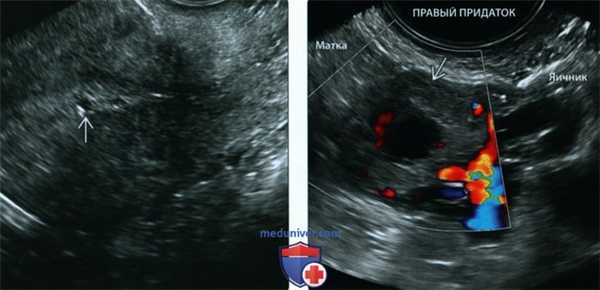

(Слева) При ТВУЗИ видна маленькая округлая кистозная структура В в пустой матке. Подобная внутриматочная структура, напоминающая плодное яйцо, по статистике, наиболее вероятно является МБ; тем не менее тщательный осмотр придатков обязателен при каждом УЗИ малого таза.

(Справа) При ТВУЗИ у той же пациентки визуализируется объемное образование придатка В без желточного мешка или эмбриона (т.е. «возможная ВМБ»), расположенное между маткой и левым яичником. Пациентка отказалась от медикаментозного лечения. При хирургическом вмешательстве была подтверждена левосторонняя трубная беременность без разрыва трубы.